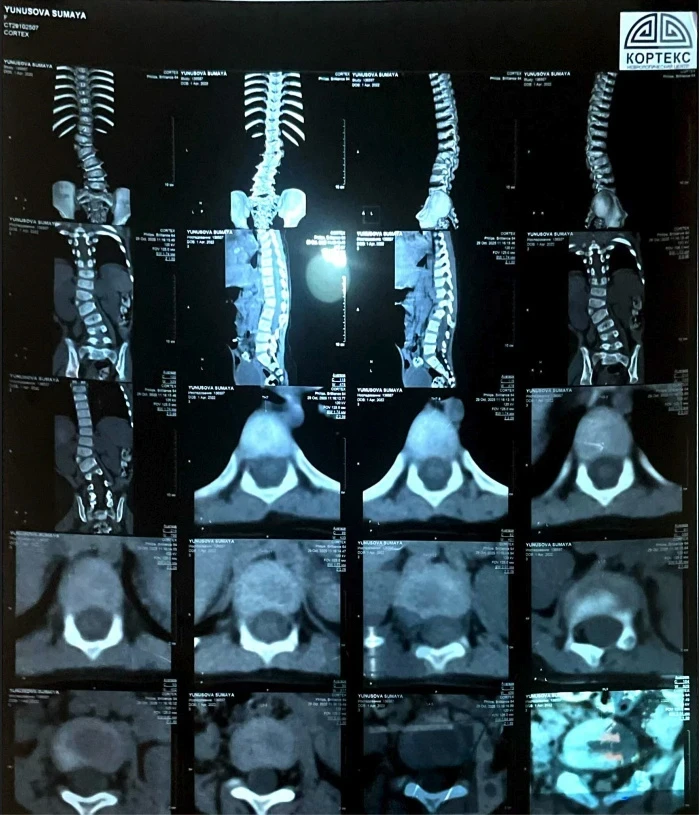

У девочки выявили сколиоз сложной формы, что вызывает у неё затруднения при ходьбе и беге, и она вынуждена проводить большую часть дня в сидячем или лежачем положении.

«Узнав, что ничего не помогает, мы обратились за консультацией к турецким профессорам. Они заявили, что единственный выход — операция, и чем быстрее она будет проведена, тем лучше для роста и развития Сумаи. Кроме того, мы узнали, что у неё есть лишняя кость на позвонке, что также является последствием сколиоза», - сообщает мама.

Сколиоз уже вызвал асимметрию тела, у Сумаи одно плечо ниже другого, а одна нога короче.